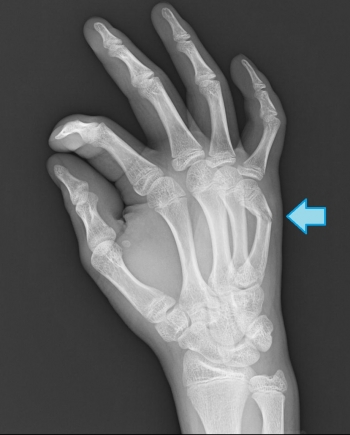

º£Æü¡¢¤´¾Ò²ð¤¹¤ë¤Î¤Ï¡¢¼ê»Ø¹ü¹üÀÞ¤ÎʬÎà¤Î¾ÜºÙ¤Ë¤Ä¤¤¤Æ¤´¾Ò²ð¤·¤Æ¤¤¤­¤¿¤¤¤È»×¤¤¤Þ¤¹¡£

¼ê»Ø¹üÀÞ¤ÎʬÎà

¼¡²ó¤Ï¡¢²¼»è¤Î¹üÀÞ¡¡¹üÈ×¹ü¹üÀÞ¤ò¤ªÏ䵤»¤Æ¤â¤é¤¤¤Þ¤¹¤Í